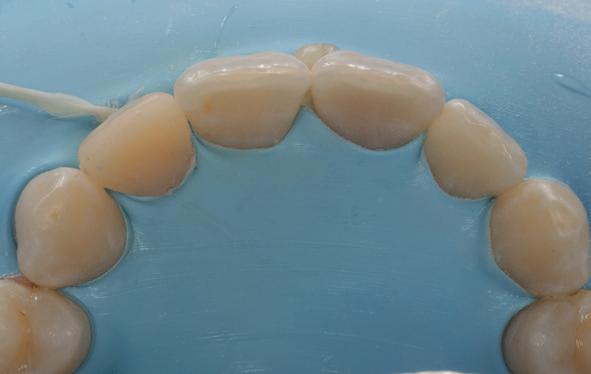

In het eerste jaar is hij regelmatig bij ons op controle geweest, daarna zagen wij hem pas weer vier jaar na het trauma (afbeelding 15-18). Hij was toen 19 jaar.

Diagnose

Persisterende niet-pijnlijke parodontitis apicalis met fistel en externe ontstekingsresorptie 13 ten gevolge van infectie.

• 12 gezonde situatie.

• Onduidelijk voor de 11, mogelijk niet-pijnlijke parodontitis apicalis 11 met ontstekingsresorptie ten gevolge van infectie.

Etsbrug onderfront, in afwachting van een implantaat.

Aangezien de prognose slecht was voor de 13, is hij verwezen naar tandarts-implantoloog Irfan Abas.

Hij heeft een CBCT-scan gemaakt en na extractie de 13 vervangen door een implantaat. Er was nog wat onduidelijkheid over de status van de 11, dus we hebben hem expliciet laten kijken naar het vermeende resorptiedefect. Dit bleek echter een groot foramen incisivum, dus een overprojectie, zelfs in de vorm van een hartje (afbeelding 19, met dank aan Irfan Abas).

Uiteindelijk zagen wij hem nog voor controle zeven jaar na het trauma, inmiddels 22 jaar.

Het klinische beeld oogde rustig, er waren (implantaatgedragen) kronen ter plaatse van de 13 en 42, geen reacties op testen (percussie/palpatie/pockets) en de reacties op koude waren bij de 21, 22, 41 en 31 normaal.

Röntgenologisch waren er evenmin bijzonderheden waar te nemen, de implantaten zagen er stabiel uit (afbeelding 20 en 21, met dank aan Irfan Abas). De diagnose was dan ook gezonde pulpae 41, 31 en geen bijzonderheden voor de overige tanden.

Bij dit trauma hebben meerdere tanden (forse) schade opgelopen aan het PDL, de pulpa en/of mogelijk aan het bot. De 13 en de 42 zijn verloren gegaan, de 12 en 11 zijn na endodontische behandelingen goed hersteld en de pulpae van de 41 en 31 zijn vitaal gebleven. Een avulsie is weliswaar het zwaarste trauma voor een tand, maar de forse luxaties en relatief late reponaties van de 12 en 11 hadden uiteindelijk ook voor meer schade kunnen zorgen en zelfs tot verlies kunnen leiden.